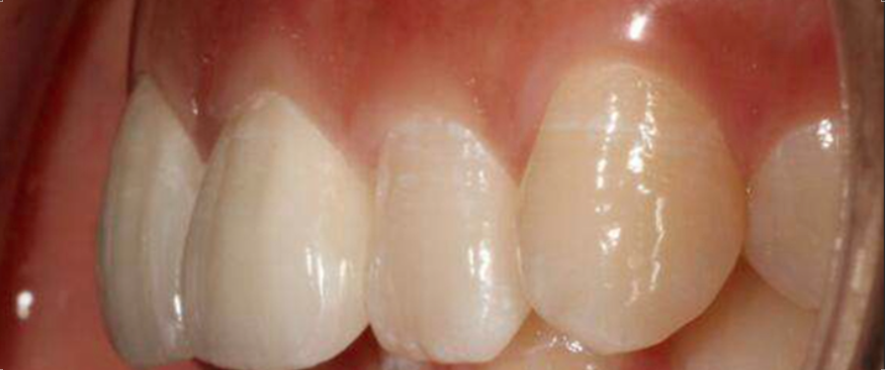

这个放射学发现得到了临床验证:在摘除囊肿后,仍然存在坚实的骨质,左侧下颌神经的放射学检查显示其解剖结构正常。为了保护下颌神经,实施了牙冠切除术,并缝合了术区。术后3个月复查未发现下牙槽神经分布区域有感觉异常,复查的全景片显示骨愈合良好,剩余牙根位置稳定。组织病理学特征与牙源性囊肿一致,囊壁存在慢性炎症浸润,并被炎性鳞状上皮覆盖。